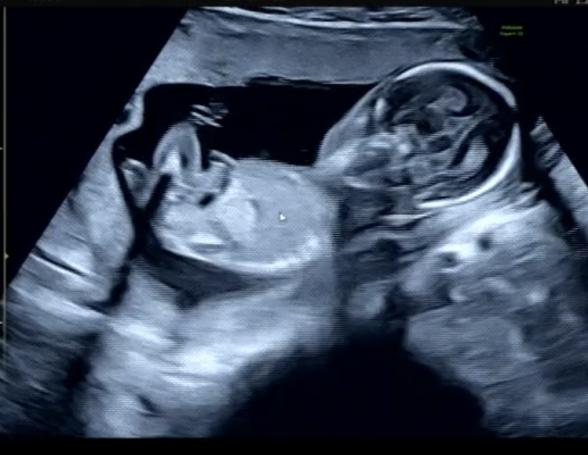

13wに胎児ドックを行った時には男の子かもと言われていましたが

17wでの検診の時には女の子だと言われました!

次の検診まで確定ではないとは言われていますが、、

拝見していて、はっきりと男の子のシンボルはわからず、女の子のサインとされるお股のあたりに見られるようになる葉っぱのマーク、サインが、添付をしてくださったものからは分かりませんでした。

せっかくたくさん載せてくださったのに、大変申し訳ありません。

また次回の健診でも先生にご確認いただけたらと思います。